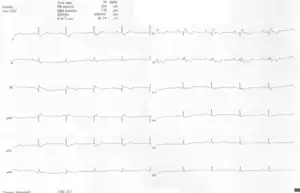

ECGs recorded during sinus rhythm and AVRT in a 9-year-old girl with Ebstein's anomaly and a Mahaim accessory pathway.

A 10-lead ECG of a woman with Ebstein's anomaly: The ECG shows signs of right atrial enlargement, best seen in V1. Other P waves are broad and tall, these are termed "Himalayan" P waves. Also, a right bundle-branch block pattern and a first-degree atrioventricular block (prolonged PR-interval) due to intra-atrial conduction delay are seen. No evidence of a Kent-bundle is seen in this patient. The T wave inversion in V1-4 and a marked Q wave in III occur; these changes are characteristic for Ebstein's anomaly and do not reflect ischemic ECG changes in this patient.